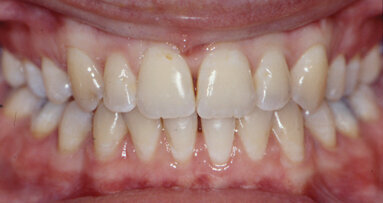

The best way to judge a system, in my opinion, is how effectively it shapes a canal without extraneous complications coming into play (Fig. 5–8).

We want to use a system that from the perspective of the canals we are shaping is most predictable in producing a shape of adequate dimensions, has minimal potential to distort the canal and no possibility of separating during its use. We cannot rely on a system that at times appears to be magnificent and at other times exacerbates our problems. The same system to be correctly designed must not only produce excellent results, but must do it consistently in all circumstances.